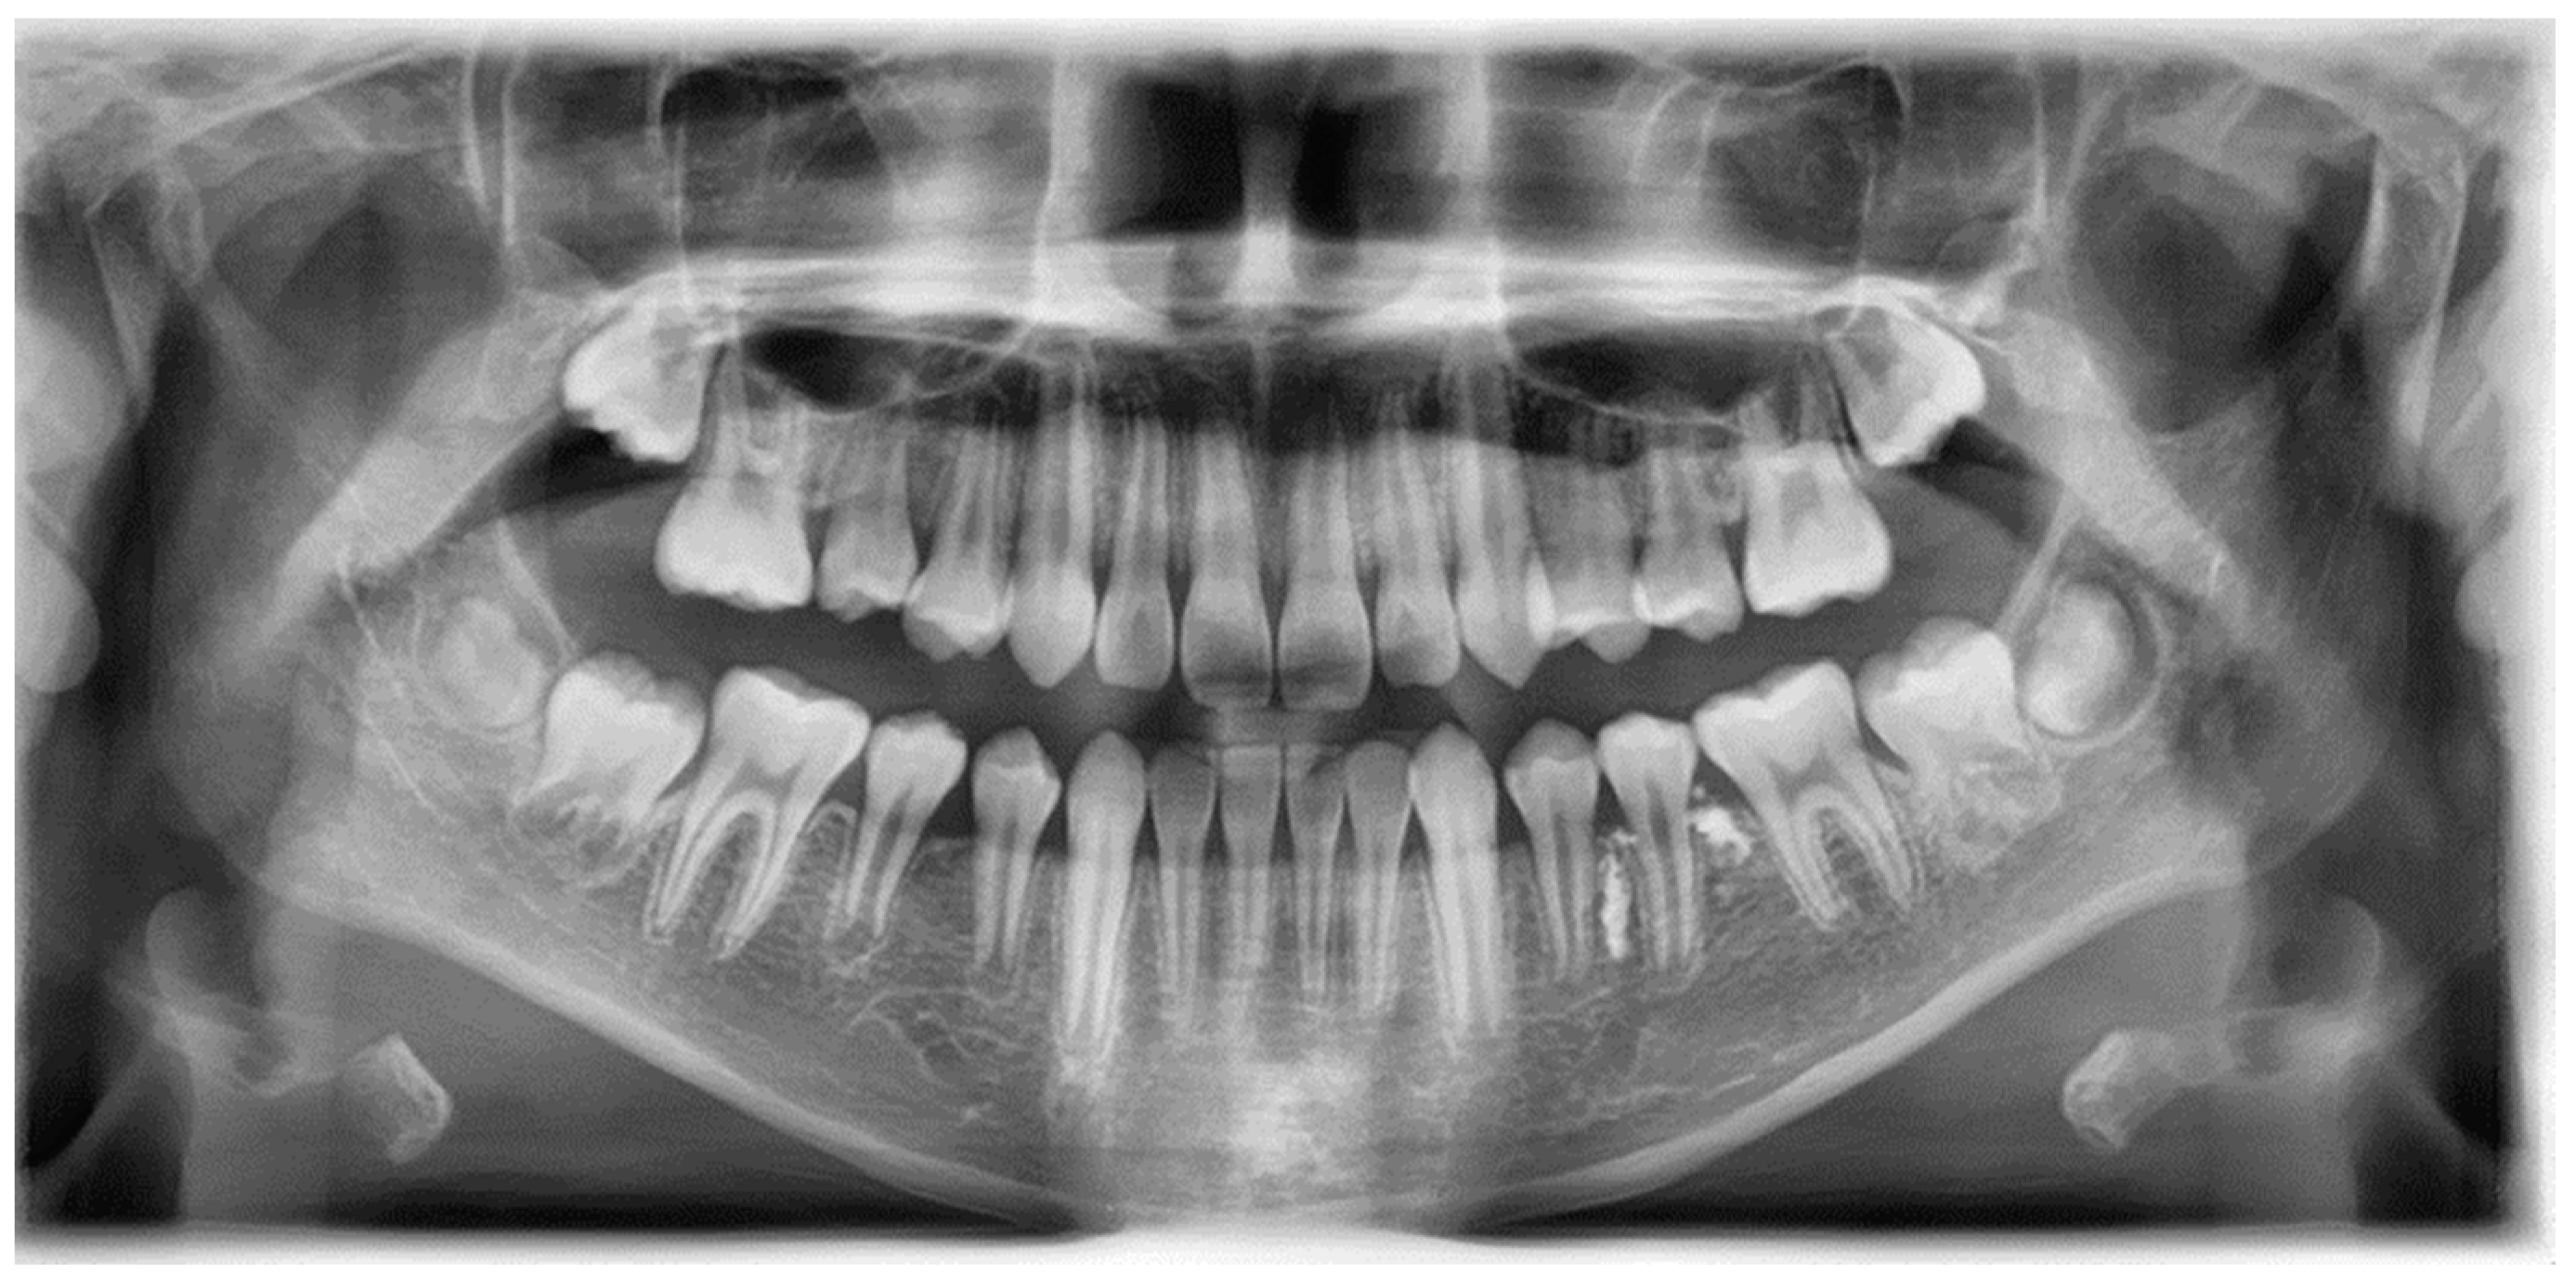

A 3-year-old girl was referred to the Department of Pediatric Dentistry of Kyung Hee University Dental Hospital at Gangdong from a local dental clinic for the treatment of periapical abscess on the left mandibular primary second molar. Her medical history was unremarkable. According to the referral from the local dental clinic, her dental history was a pulpectomy with root canal filling with Vitapex® on the affected tooth 7 months ago, and re-treatment (pulpectomy with root canal filling with Vitapex®) and temporary restoration conducted 2 days ago due to a periapical abscess. Dental examination showed a buccal sinus tract and gingival swelling in the left mandibular primary second molar with a temporary restoration state. Radiological examination revealed root resorption and a significant extrusion of the filling material (Vitapex®) from the apex, affecting the area of the successive tooth germ (Figure 1a).

Figure 1.

Periapical radiograph of left mandibular primary molar area: (a) initial visit; (b) two months after the extraction; (c) eleven months after the extraction; (d) three years after the extraction.

Two months after extraction, most of the extruded material was resorbed, but there was a small amount left near the successive tooth germ (Figure 1b). Eleven months after extraction, radiological examination showed the underdevelopment of permanent successive tooth germ compared to the opposite side (Figure 1c and Figure 2).

Figure 2.

Eleven months after tooth extraction. Panoramic radiograph. The underdevelopment of the left mandibular second premolar tooth germ (red arrow) was observed compared with the opposite one (blue arrow).

A band and loop space maintainer was delivered after the eruption of the left mandibular first molar. Three years after the extraction, the development of the successive permanent tooth was observed (Figure 1d). Four years post-extraction, the successive tooth was in the pre-eruptive phase, with continuous growth and pre-eruptive movement in the alveolar bone, similar to those in the opposite tooth (Figure 3).

Figure 3.

Four years after tooth extraction. Panoramic radiograph. Development of successive permanent tooth was observed (pre-eruptive phase).